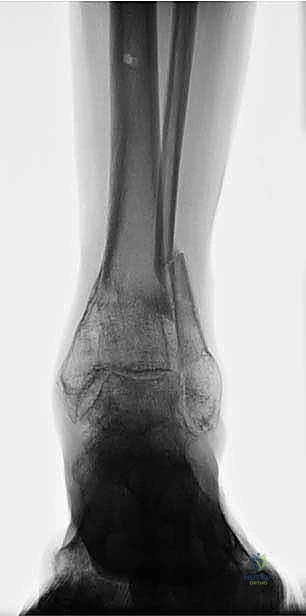

وهي السبب الأكثر شيوعاً في العيادات. عندما يتعرض المريض لكسر في أسفل الساق (مثل كسور الكاحل المعقدة أو كسور البيلون) ولا يتم علاجه بشكل صحيح، يلتئم العظم في وضعية خاطئة. هذا يُعرف بـ "سوء الالتحام" (Malunion).

أنواع التشوهات الميكانيكية في الساق البعيدة

التشوه نادراً ما يكون بسيطاً أو في اتجاه واحد. العظام هياكل ثلاثية الأبعاد، والتشوه غالباً ما يكون مركباً. يقوم الأستاذ الدكتور محمد هطيف بتحليل هذه التشوهات بدقة رياضية متناهية:

- التقوس للداخل (Varus Deformity): انحراف مفصل الكاحل والقدم نحو الداخل. يؤدي إلى ضغط هائل على الجزء الداخلي من غضروف الكاحل.

- التقوس للخارج (Valgus Deformity): انحراف مفصل الكاحل والقدم نحو الخارج. يؤدي إلى تمدد الأربطة الداخلية وتآكل الغضروف الخارجي.